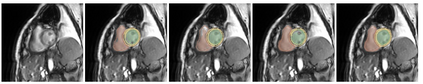

Transformer, the latest technological advance of deep learning, has gained prevalence in natural language processing or computer vision. Since medical imaging bear some resemblance to computer vision, it is natural to inquire about the status quo of Transformers in medical imaging and ask the question: can the Transformer models transform medical imaging? In this paper, we attempt to make a response to the inquiry. After a brief introduction of the fundamentals of Transformers, especially in comparison with convolutional neural networks (CNNs), and highlighting key defining properties that characterize the Transformers, we offer a comprehensive review of the state-of-the-art Transformer-based approaches for medical imaging and exhibit current research progresses made in the areas of medical image segmentation, recognition, detection, registration, reconstruction, enhancement, etc. In particular, what distinguishes our review lies in its organization based on the Transformer's key defining properties, which are mostly derived from comparing the Transformer and CNN, and its type of architecture, which specifies the manner in which the Transformer and CNN are combined, all helping the readers to best understand the rationale behind the reviewed approaches. We conclude with discussions of future perspectives.